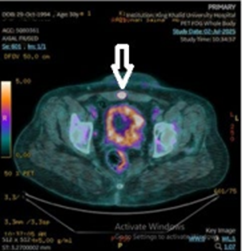

Immediately after the 2023 surgery, pathology showed a low-grade endometrioid carcinoma (NOS) confined to the endometrium with shallow myometrial invasion (about 0.3 cm, ~20% of myometrial thickness), no serosal involvement, and no lymphovascular invasion. All margins were negative, and regional lymph nodes were negative (0/7). Adenomyosis was present with focal carcinoma involvement. Over the ensuing years, routine surveillance imaging did not reveal overt metastasis until 2025, when CT CAP suggested a mild left pelvic sidewall lymph node enlargement (~1 cm), raising concern for recurrence. A subsequent PET-CT in July 2025 showed an intensely hypermetabolic left pelvic sidewall lymph node and a new anterior deep subcutaneous pelvic lesion, both highly suspicious for metastatic disease, with no distant FDG avid sites identified (Figure 2). An IR-guided biopsy of the abdominal wall lesion in July 2025 confirmed metastatic adenocarcinoma with an immunoprofile compatible with gynecologic origin (CK7+, PAX-8+, ER+, CK20−, GATA-3−, TTF-1−, wild-type p53).

Figure 2: Axial FDG-PET/CT showing a focally hypermetabolic lesion in the left rectus abdominis muscle, consistent with active disease involvement.